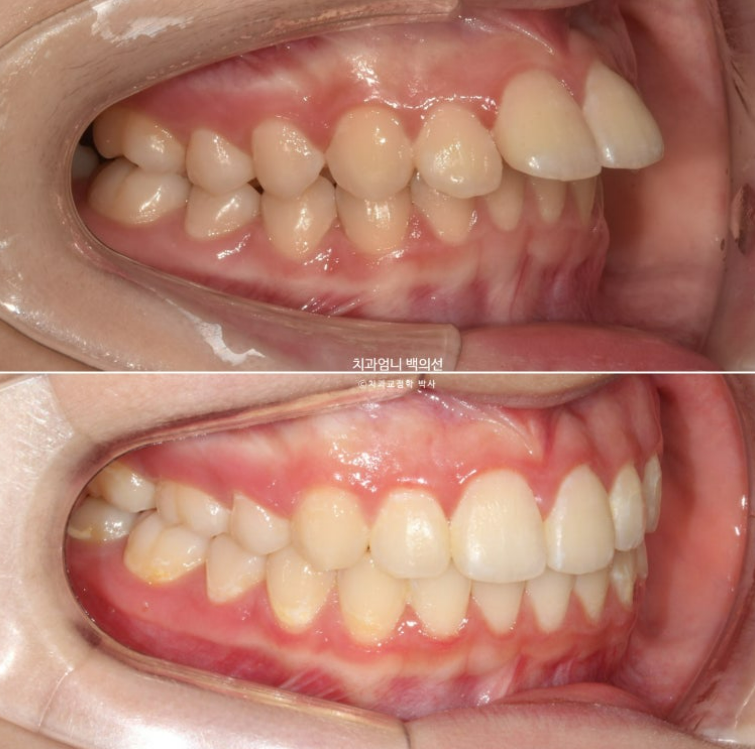

23.09

앞니가 두 개가 아주 커보입니다.

사실 환자분의 앞니가 크진 않습니다. 치아는 입안에서 철저한 원근법을 따르기 때문에 위치적으로 다른 치아에 비하여 앞으로 튀어나와 있으면 상대적으로 커보입니다.

앞니 돌출이 심한편입니다.

돌출이 위에만 국한되어 있어 위에만 작은어금니 2개 발치 후 교정하기로 했습니다.

클리피씨 교정기를 선택하셨고 치료에 들어갔습니다.

치료시작 9개월째 모습입니다.